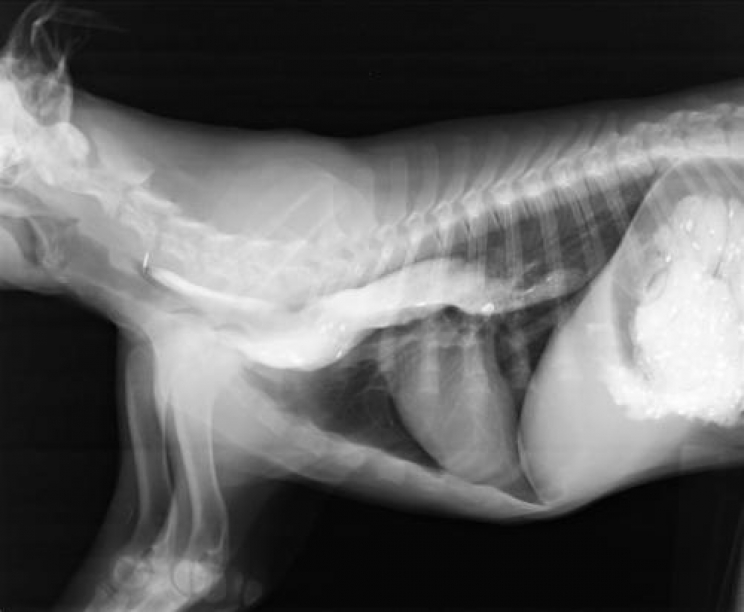

La diagnosi poi è semplice, viene fatto ingerire al cane un "pasto opaco" (che si vede nelle radiografie) e viene effettuata la radiografia dopo qualche minuto: se il cibo opaco è sempre in esofago e non procede la diagnosi è quella.

megaesofago2